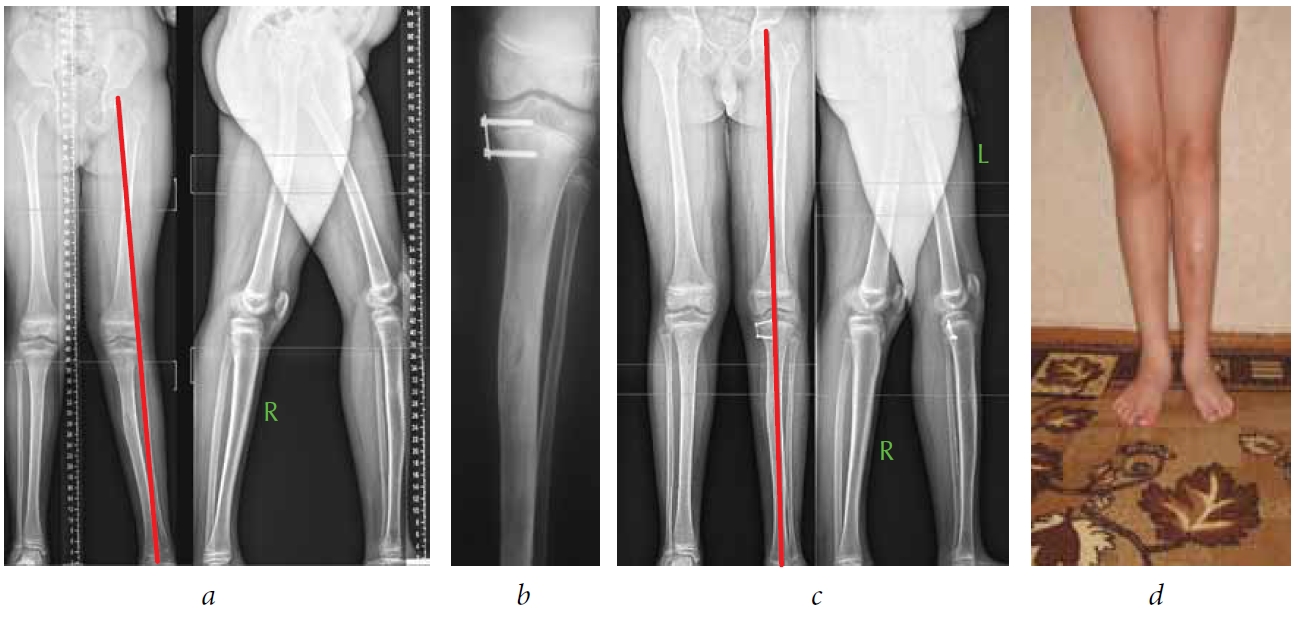

Patient P., age 5 years, was admitted to the clinic of the Turner Scientific and Research Institute for Children’s Orthopedics with a diagnosis of congenital malformation of the right lower extremity. The patient had shortening of the right lower extremity by 6.5 cm with valgus-torsion deformity of the femur and fibular hemimelia (ectromelia) of the right tibia. At admission, the patient and the mother complained of deformity and shortening of the right tibia. After examination and analysis of panoramic radiographs (Fig. 1), we found that the patient had a valgus deformity of the right femur with apex at the level of the knee joint, shortening of the right femur by 5 cm and that of tibia by 1.5 cm. As per CT data, the right thigh also has a torsional deformation component equal to 20°. According to the practical classification, the deformity was regarded as a deformity with an average degree of complexity. Before correction, the distal mechanical angle of the femur was 80°, the anatomical posterior distal angle of the femur was 79°, and the deviation of the mechanical axis was 22 mm outwards.

Fig. 1. Patient P. at the first stage of treatment: а — preoperative panoramic radiographs of the lower extremities; b — a common mechanical axis of the limb is drawn on a panoramic radiograph; c — on the radiograph, mechanical axes of the proximal and distal bone fragments are drawn, the apex of the deformity was found; d — panoramic radiographs of the lower extremities at the end of the first stage (before removing the figure-of-eight plate)

According to radiographs and CT images, there was marked hypoplasia of the lateral condyle of the right femur. Considering the localization of the deformity, patient age, hypoplasia of the lateral condyle and the external torsion of the femur, we decided to perform two-stage deformity correction. The first stage was temporary hemiepiphysiodesis of the inner portion of the distal growth zone of the right femur with a figure-of-eight plate for eliminating the varus component of the deformity and level the size of the femoral condyles. The postoperative period was uneventful. The function of the knee joint at the time of hospital discharge (5 days postoperatively) was complete. The patient was followed up every 3 months. The deformity was eliminated (Fig. 1, d), and the plate was removed 380 days after the primary surgery.